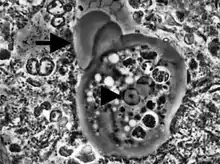

| Entamoeba histolytica trophozoite | |

Entamoeba cells are small, with a single nucleus and typically a single lobose pseudopod taking the form of a clear anterior bulge. They have a simple life cycle. The trophozoite (feeding-dividing form) is approximately 10-20 μm in diameter and feeds primarily on bacteria. It divides by simple binary fission to form two smaller daughter cells. Almost all species form cysts, the stage involved in transmission (the exception is Entamoeba gingivalis). Depending on the species, these can have one, four or eight nuclei and are variable in size; these characteristics help in species identification.